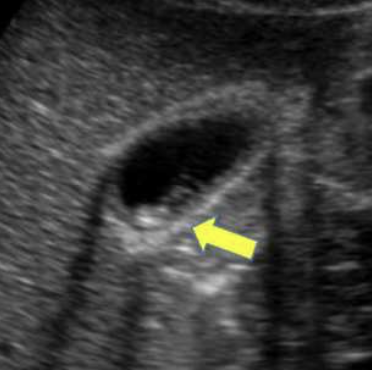

what is shown?

cervix sign in transverse indicating hypertrophic pyloric stenosis (HPS)

target sign in longitudinal plane indicating hypertrophic pyloric stenosis (HPS)